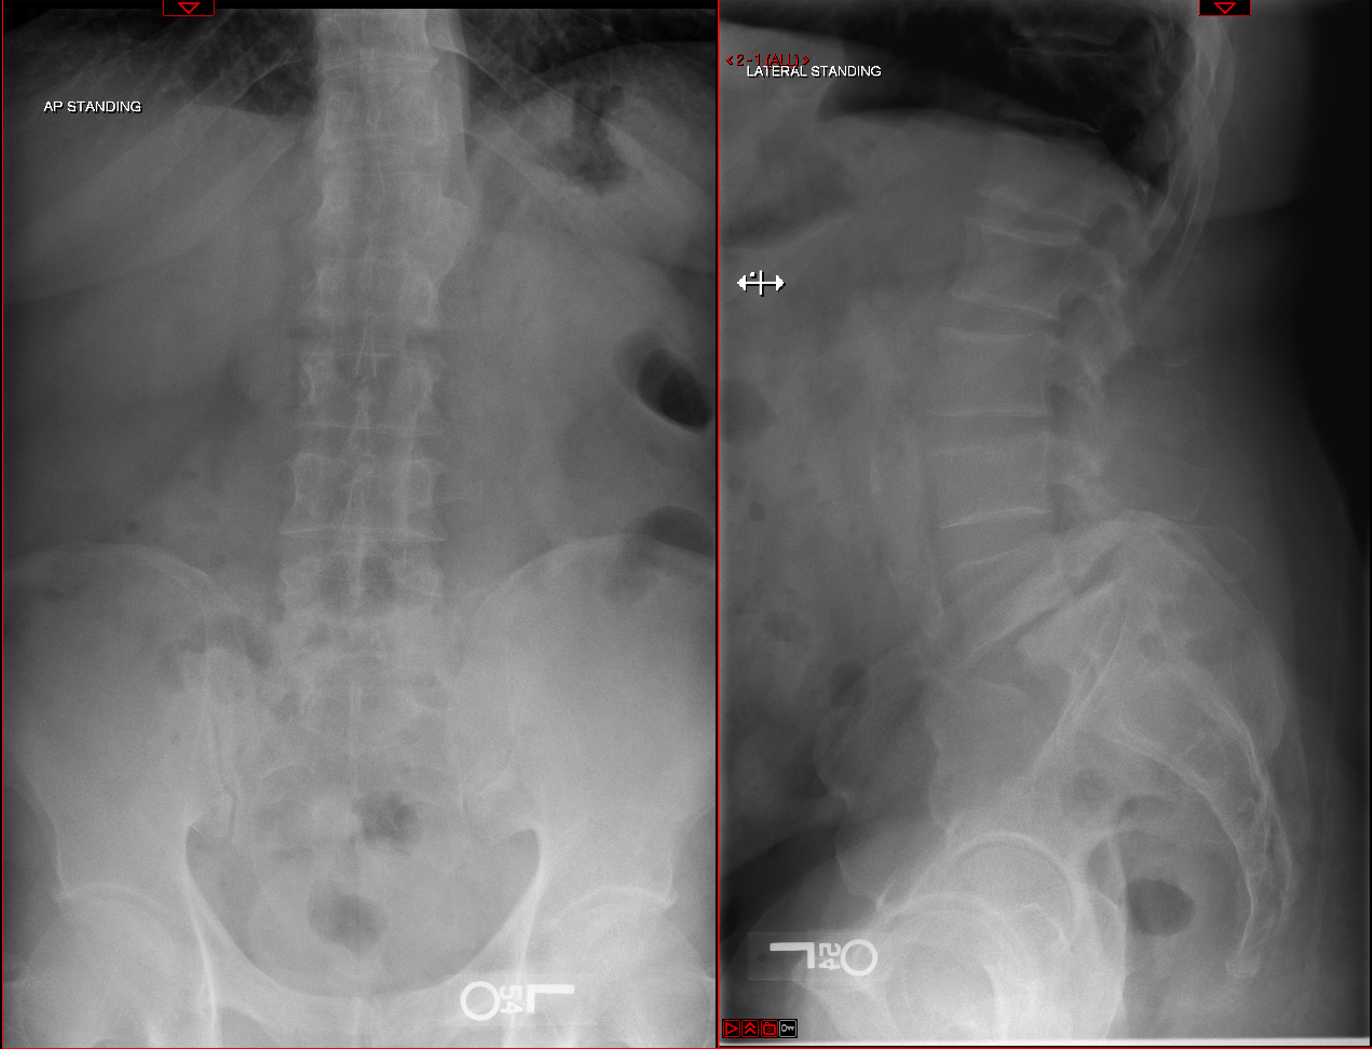

Transforaminal Lumbar Spine Fusion